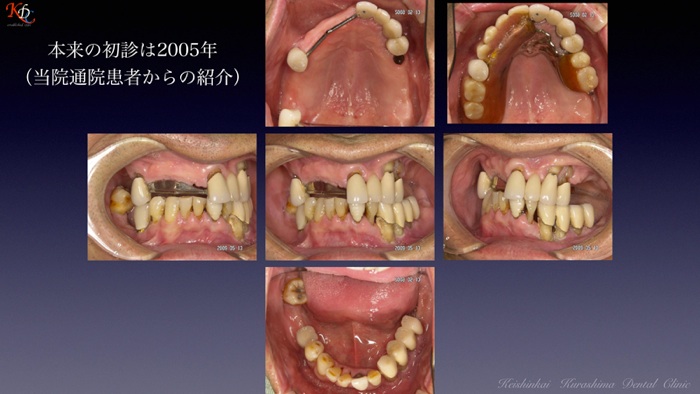

咬合再建・咬合回復shapeimage_22_link_0

症例に応じた治療手法の選択と咀嚼機能再現の効果http://www.kura-dent.com/Treatment%20and%20effects.pdfshapeimage_23_link_0